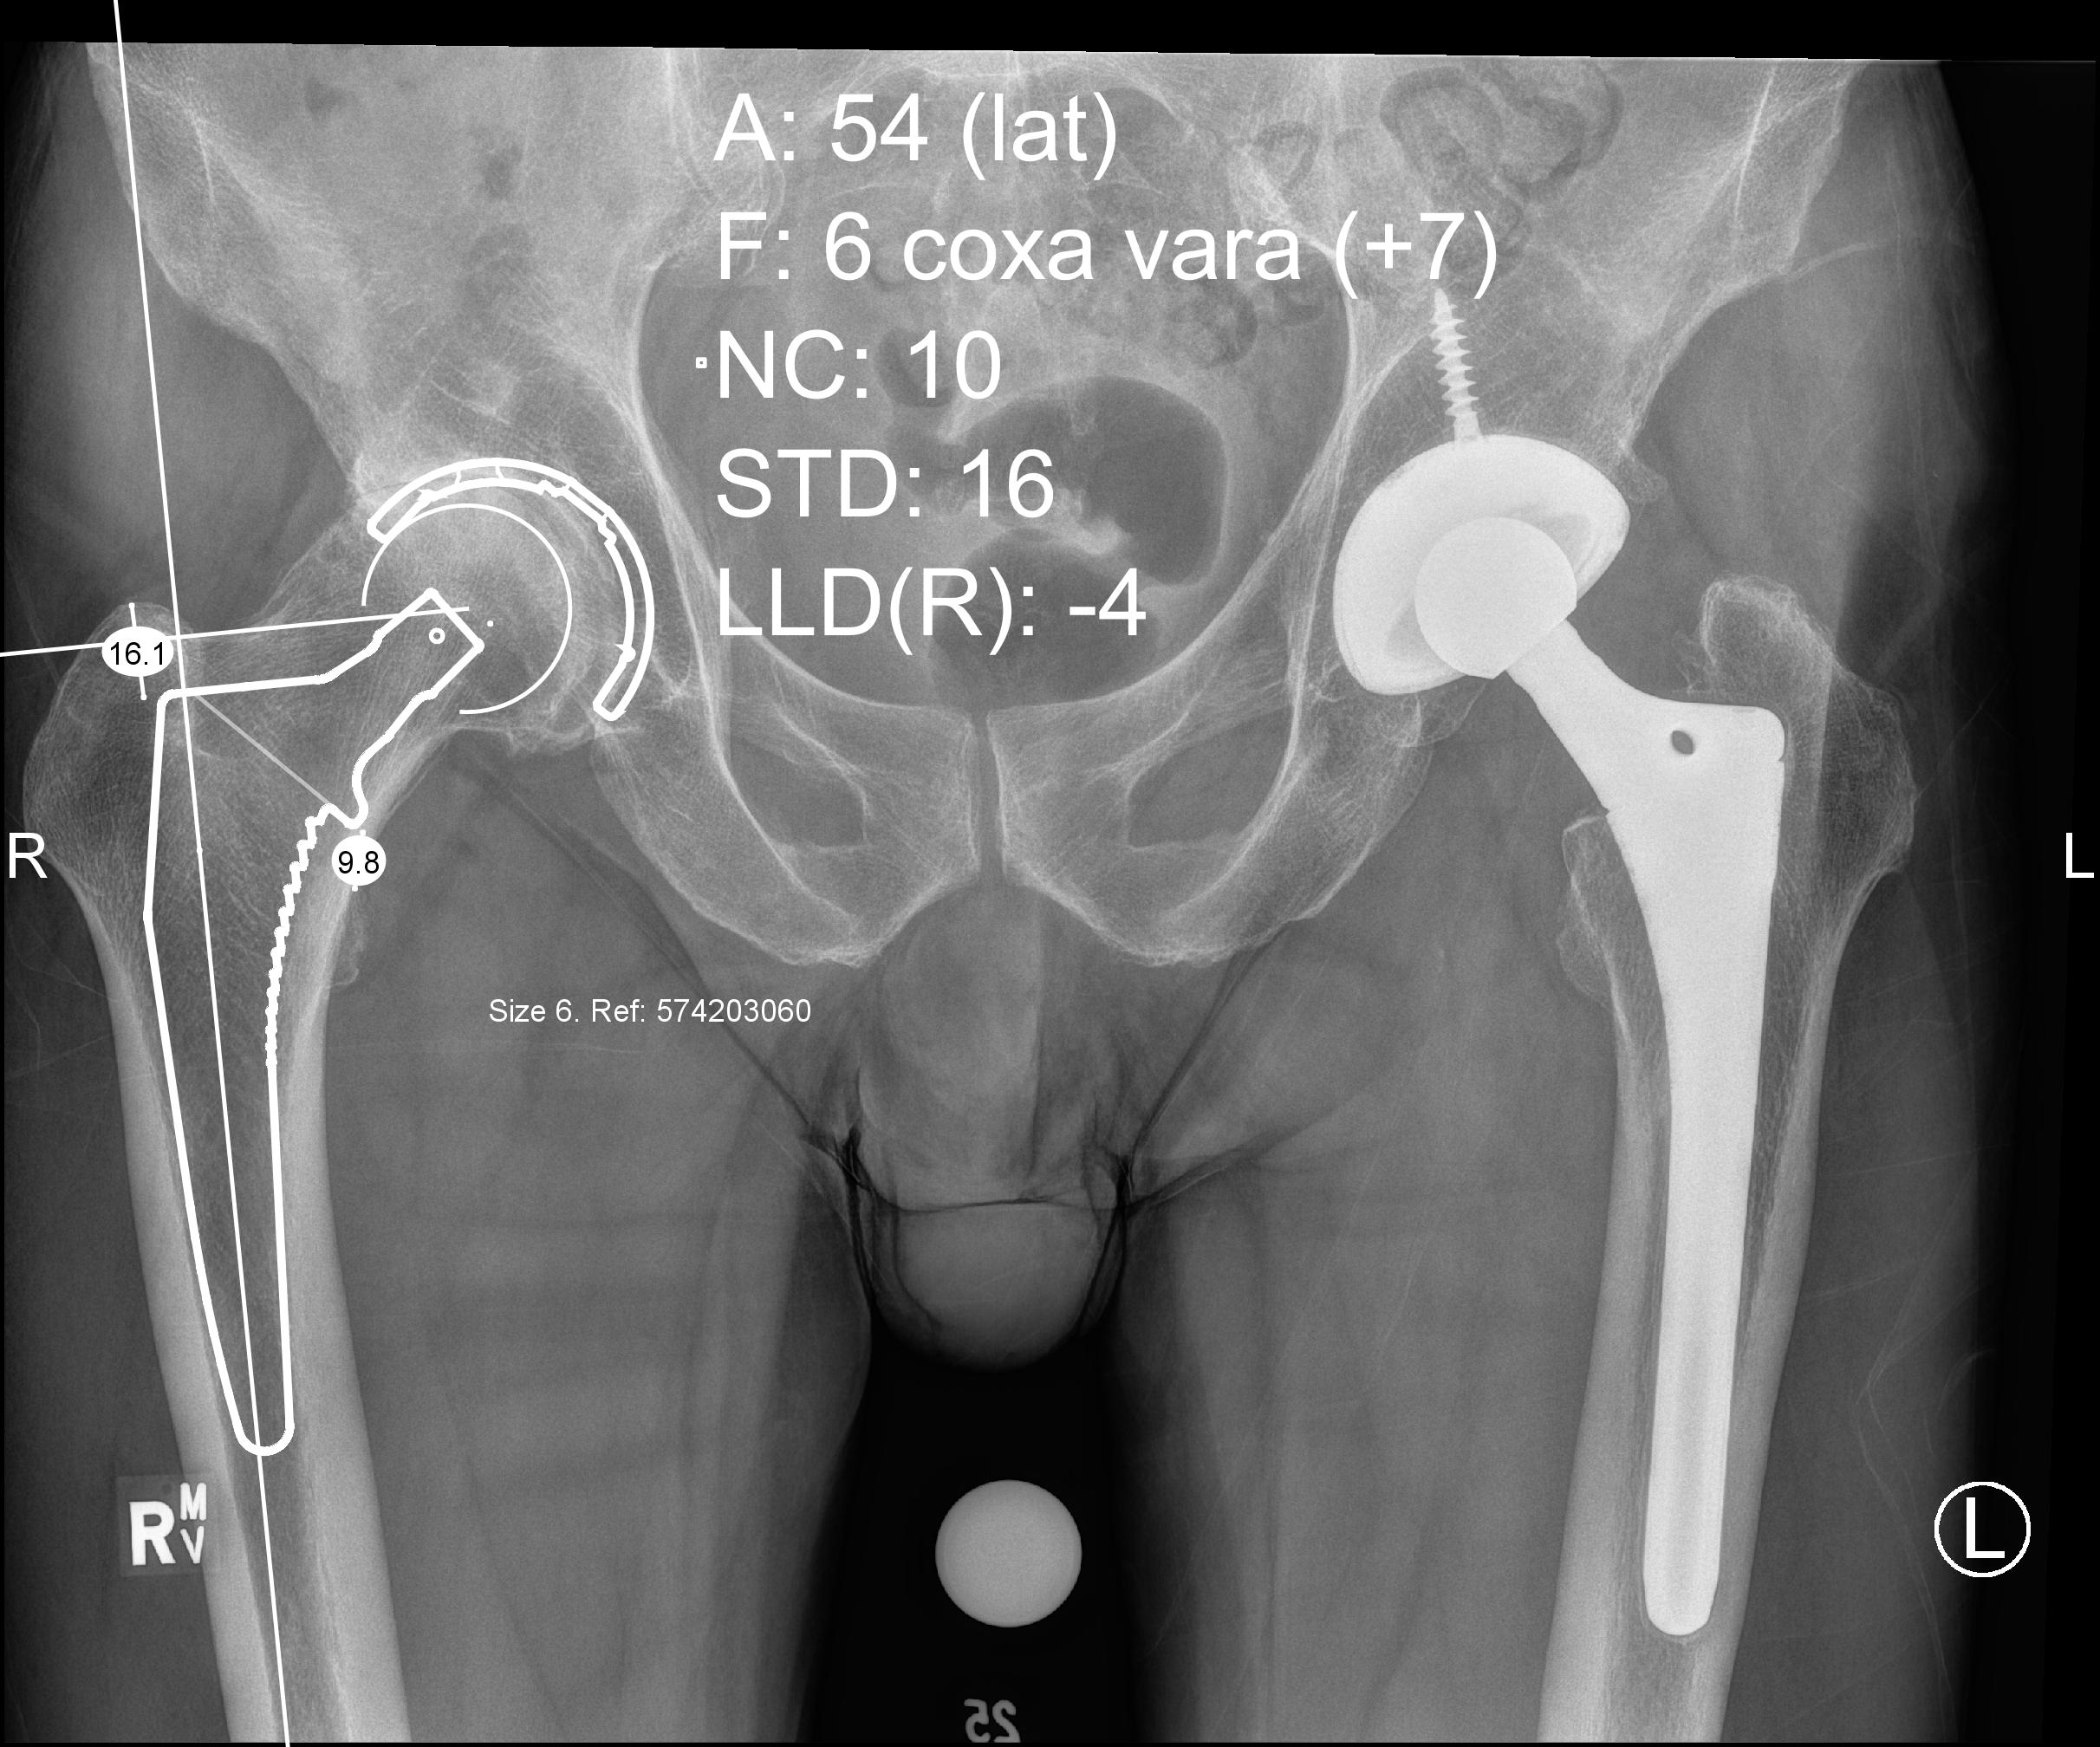

1. AP pelvis

2. Lower extremities internally rotated 15° to 20°

- accounts for femoral anteversion

- allows offset templating

3. Magnification marker

- degree of magnification directly related to distance from bone to cassette

- typical magnification of 15% to 20%

- also varies with patient size

- larger patients increased magnification, smaller patients reduced magnification